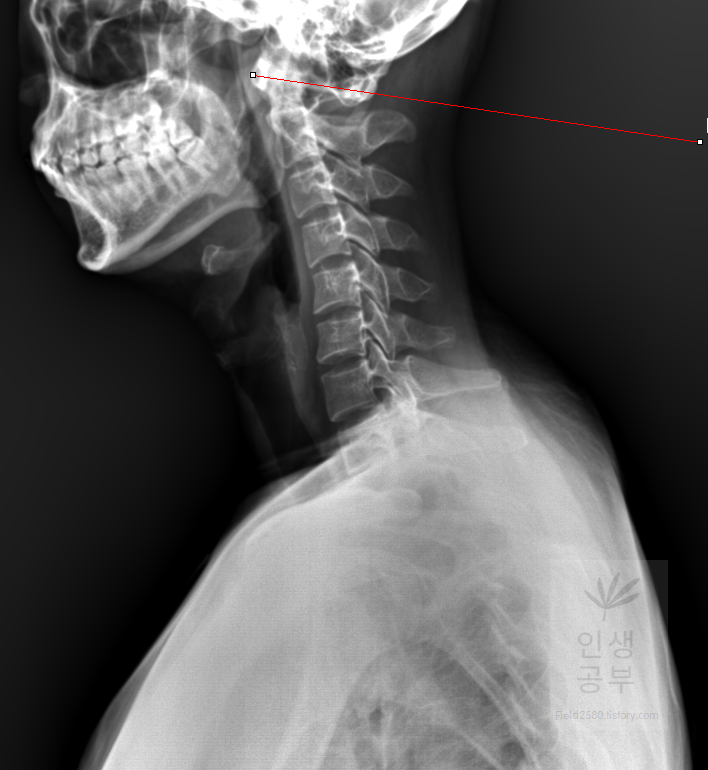

선 긋기를 이용해서 Cobb각을 그린다고 가정했을 때 측정하려고 하는 곳을 처음에 누르고 드래그로 쭉 끌어다주면 위와 같은 선이 생기고 선의 길이가 자동으로 측정됩니다. 첫 번째 목뼈(C1) 선을 그리기 위해 제일 튀어나온 앞쪽 부분 가운데 지점에(Center of Anterior arch) 점을 찍어줍니다. 후궁(Posterior arch) 제일 좁은 부위 가운데 지점에 점을 찍어줍니다. 두 점을 연결해주는 선을 그어줍니다. 이 선 이름을 고리 뼈 선(APL : Atlas Plane Line)이라고 합니다. 점은 조금 더 정확하기 위해서 하는 것이 찍어도 되고, 점을 찍지 않은 상태에서 선을 그으셔도 무방합니다.

위쪽에 있는 선은 첫 번째 목뼈(C1) 선을 그리기 위해 제일 튀어나온 앞쪽 부분 가운데 지점에(Center of Anterior arch)에서 시작해서 후궁(Posterior arch) 제일 좁은 부위 가운데를 지나는 선이 되도록 이동해줍니다. 선 이름을 고리 뼈 선(APL : Atlas Plane Line)이라고 합니다. 점은 조금 더 정확하기 위해서 하는 것이 찍어도 되고, 점을 찍지 않은 상태에서 선을 그으셔도 무방합니다. 아래쪽에 있는 선은 일곱번째 목뼈 추체 밑면(Inferior endplate of C7)과 평행하게 선을 맞춰줍니다. 노란색 글자와 숫자가 아래줄 맞춰 준 곳에 있는데 A는 Angle 각도이고 옆에 있는 숫자가 Cobb 각입니다.